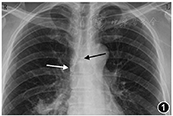

患者返回血管通道中心,重新对穿刺部位导管和皮肤进行消毒,根据胸部X线片上电子标尺测量导管打折长度约2.5 cm,故将导管从静脉中拔出3 cm,然后重新送入导管。连接科曼C100心电定位仪,4个电极片分别贴于右锁骨下(RA)、左锁骨下(LA)、左下(LL)腹部、右下(RL)腹部,屏幕抓取二导联心电波形原始资料记录患者基础心电图,取下RA导联,将无菌导联线鳄鱼夹一端夹在20 ml注射器注射针头针柄上,一端连接心电定位仪,采用生理盐水引导腔内心电图定位方法,心电图显示P波高尖,P波振幅等于QRS波振幅的1/2(图2),提示导管尖端位于SVC中、下三分之一。随后拍摄的CXR显示导管尖端位于SVC中段,导管末端仍然反折成L型(图3)。故进行第二次导管尖端位置调整,在心电图定位下,拔出部分导管,直到高P波消失。然后轻柔缓慢将导管再次送入血管至导管0刻度位置,观察P波振幅从正常到高尖,但未观察到负向P波改变,继续将导管0刻度后1 cm长度导管送入血管,观察到高尖P波前有一个负向小P波,即双向P波(图4)。最后,将导管拔出1 cm,导管外露0刻度。再次拍摄的CXR显示导管尖端位于SVC的下三分之一处(图5)。